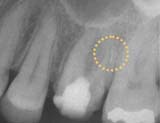

■異物の除去■

施術前

異物

施術後

「施術前」の写真は、他院から紹介で受診された患者さんのものです。治療中には不測の事態が起きることがあります。

写真には治療用の器具が写っています。

折れた器具を技術を駆使して取り去り、通常通り根を薬で詰めて治療は完了します。